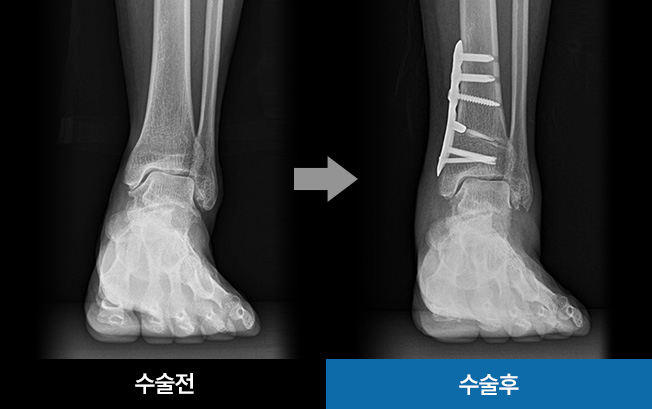

발목 연골 한쪽만 닳아 발생하는 발의 기울어짐을 교정하고,

손상된 연골 부위의 압력을 줄여주기 위해 체중이 정상적인

연골 부위로 분산되도록 축을 이동시키는 수술법입니다.

수술시간 약 1시간

발목 압력 해소 기대